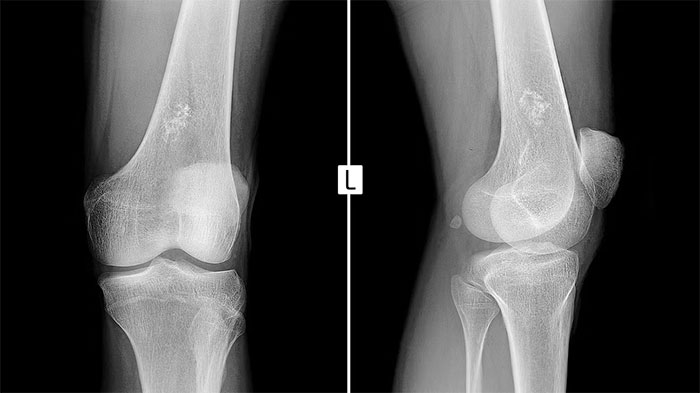

تشخیص سارکوم یوئینگ فرایندی چندمرحلهای است که نیاز به بررسی دقیق توسط تیم پزشکی متخصص دارد. نخستین گام معمولاً تصویربرداری با استفاده از اشعه ایکس است که نشاندهنده ضایعات غیرطبیعی در استخوان خواهد بود. پس از آن، روشهای دقیقتر مانند امآرآی (MRI) و سیتی اسکن برای تعیین اندازه، محل و میزان درگیری بافتهای اطراف به کار میروند. اسکن استخوان با رادیونوکلئید نیز برای بررسی گسترش احتمالی سرطان در سایر نقاط استخوانی انجام میشود.